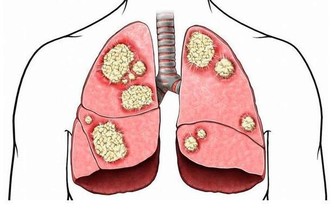

我們可以通過飲食來補氣血,例如:可以多食用牛肉、枸杞、白扁豆等來補氣,可以食用烏骨雞、黑芝麻、龍眼肉等來補血。